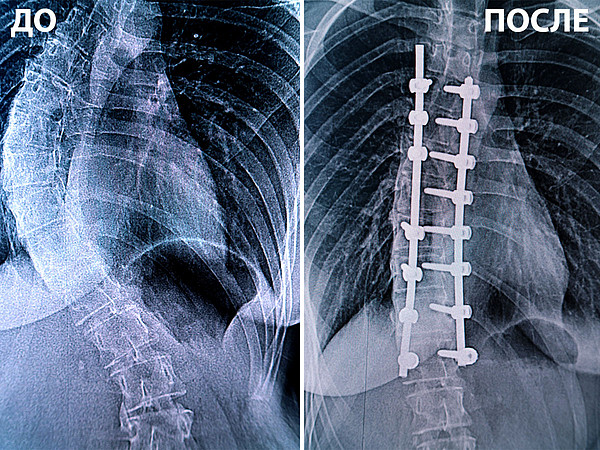

до-после.